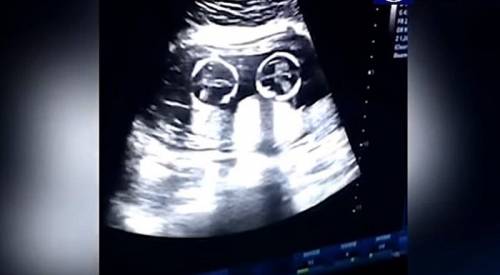

En ella se ve una "pelea de gemelas" dentro del útero de su madre.

El video fue captado durante una visita de rutina al doctor a los cuatro meses de gestación.

En las imágenes se ve como si las bebés están discutiendo.

Las bebés fueron llamadas Cherry y Strawberry y el video ya se compartió millones de veces.